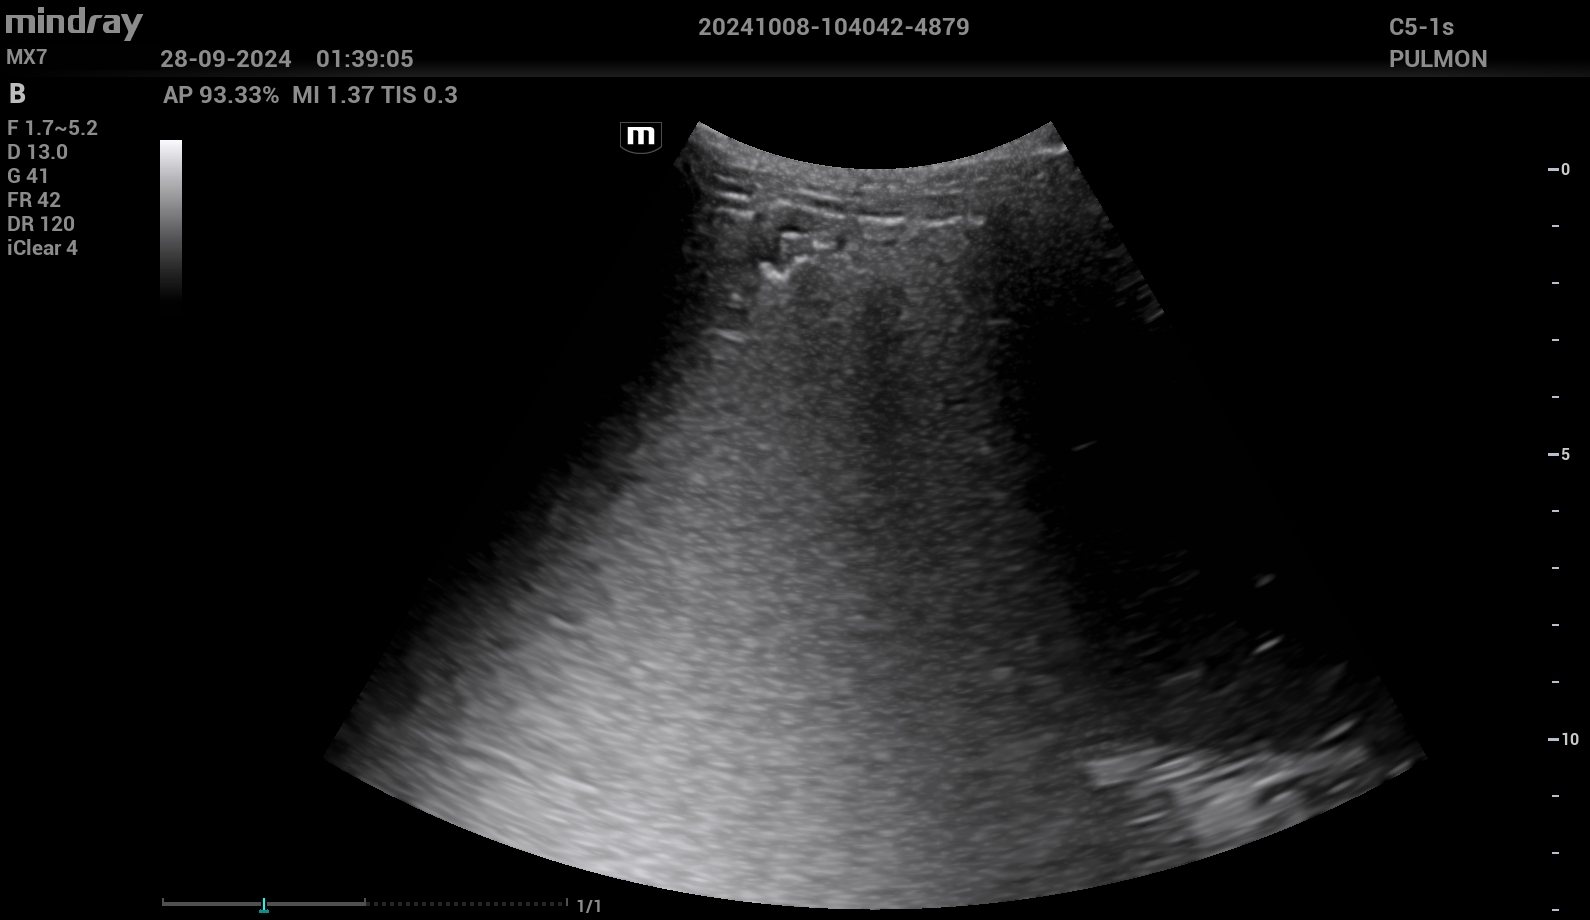

Se completa estudio con ecografía pulmonar a pie de cama, que muestra Sliding conservado, con patrón de líneas B en base y campo medio derecho, con una pequeña consolidación subpleural en base derecha. En base izquierda, consolidación pulmonar, con hepatización, y derrame pleural asociado.